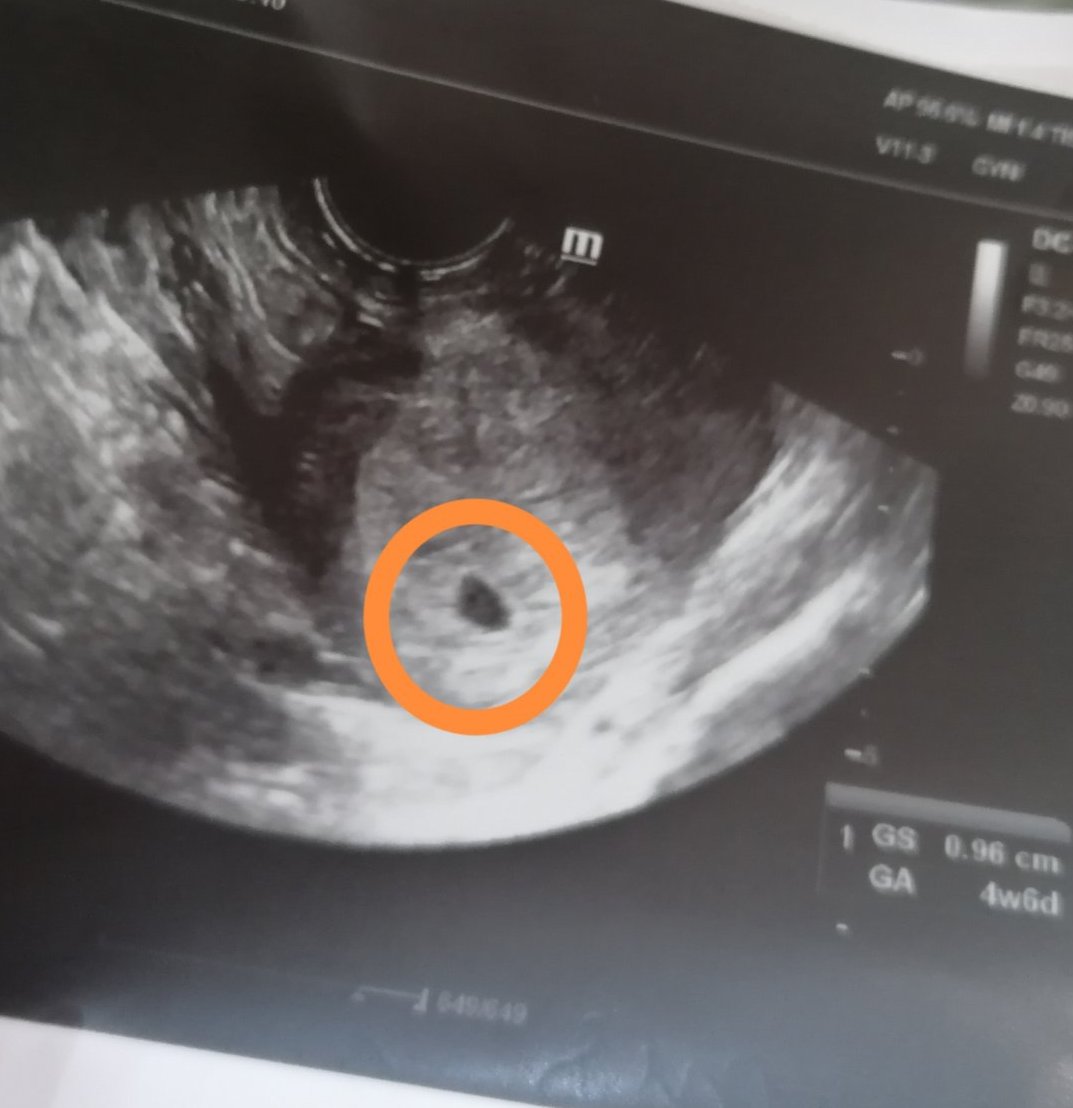

Здравейте! Връщам се от втория си преглед и вече се вижда жълтъчно мехурче и доколкото разбрах сак. Всичко е с размер 9,6 мм. АГ каза, че всичко е наред и заради дългия ми цикъл е толкова малка седмицата. Ехографът я определя като 4 седмица и 6 дни. Изпрати ме и на ПКК, урина, кръвна захар, кръвна група и резос фактор. Каза след две седмици пак на преглед, но аз имам записан час при моята си лекарка за другата неделя. Изключително се радвам, че вече ми е потвърдена бременността! Пожелавам хубави резултати на всички! ❤️ Добавям и снимка 😊😊